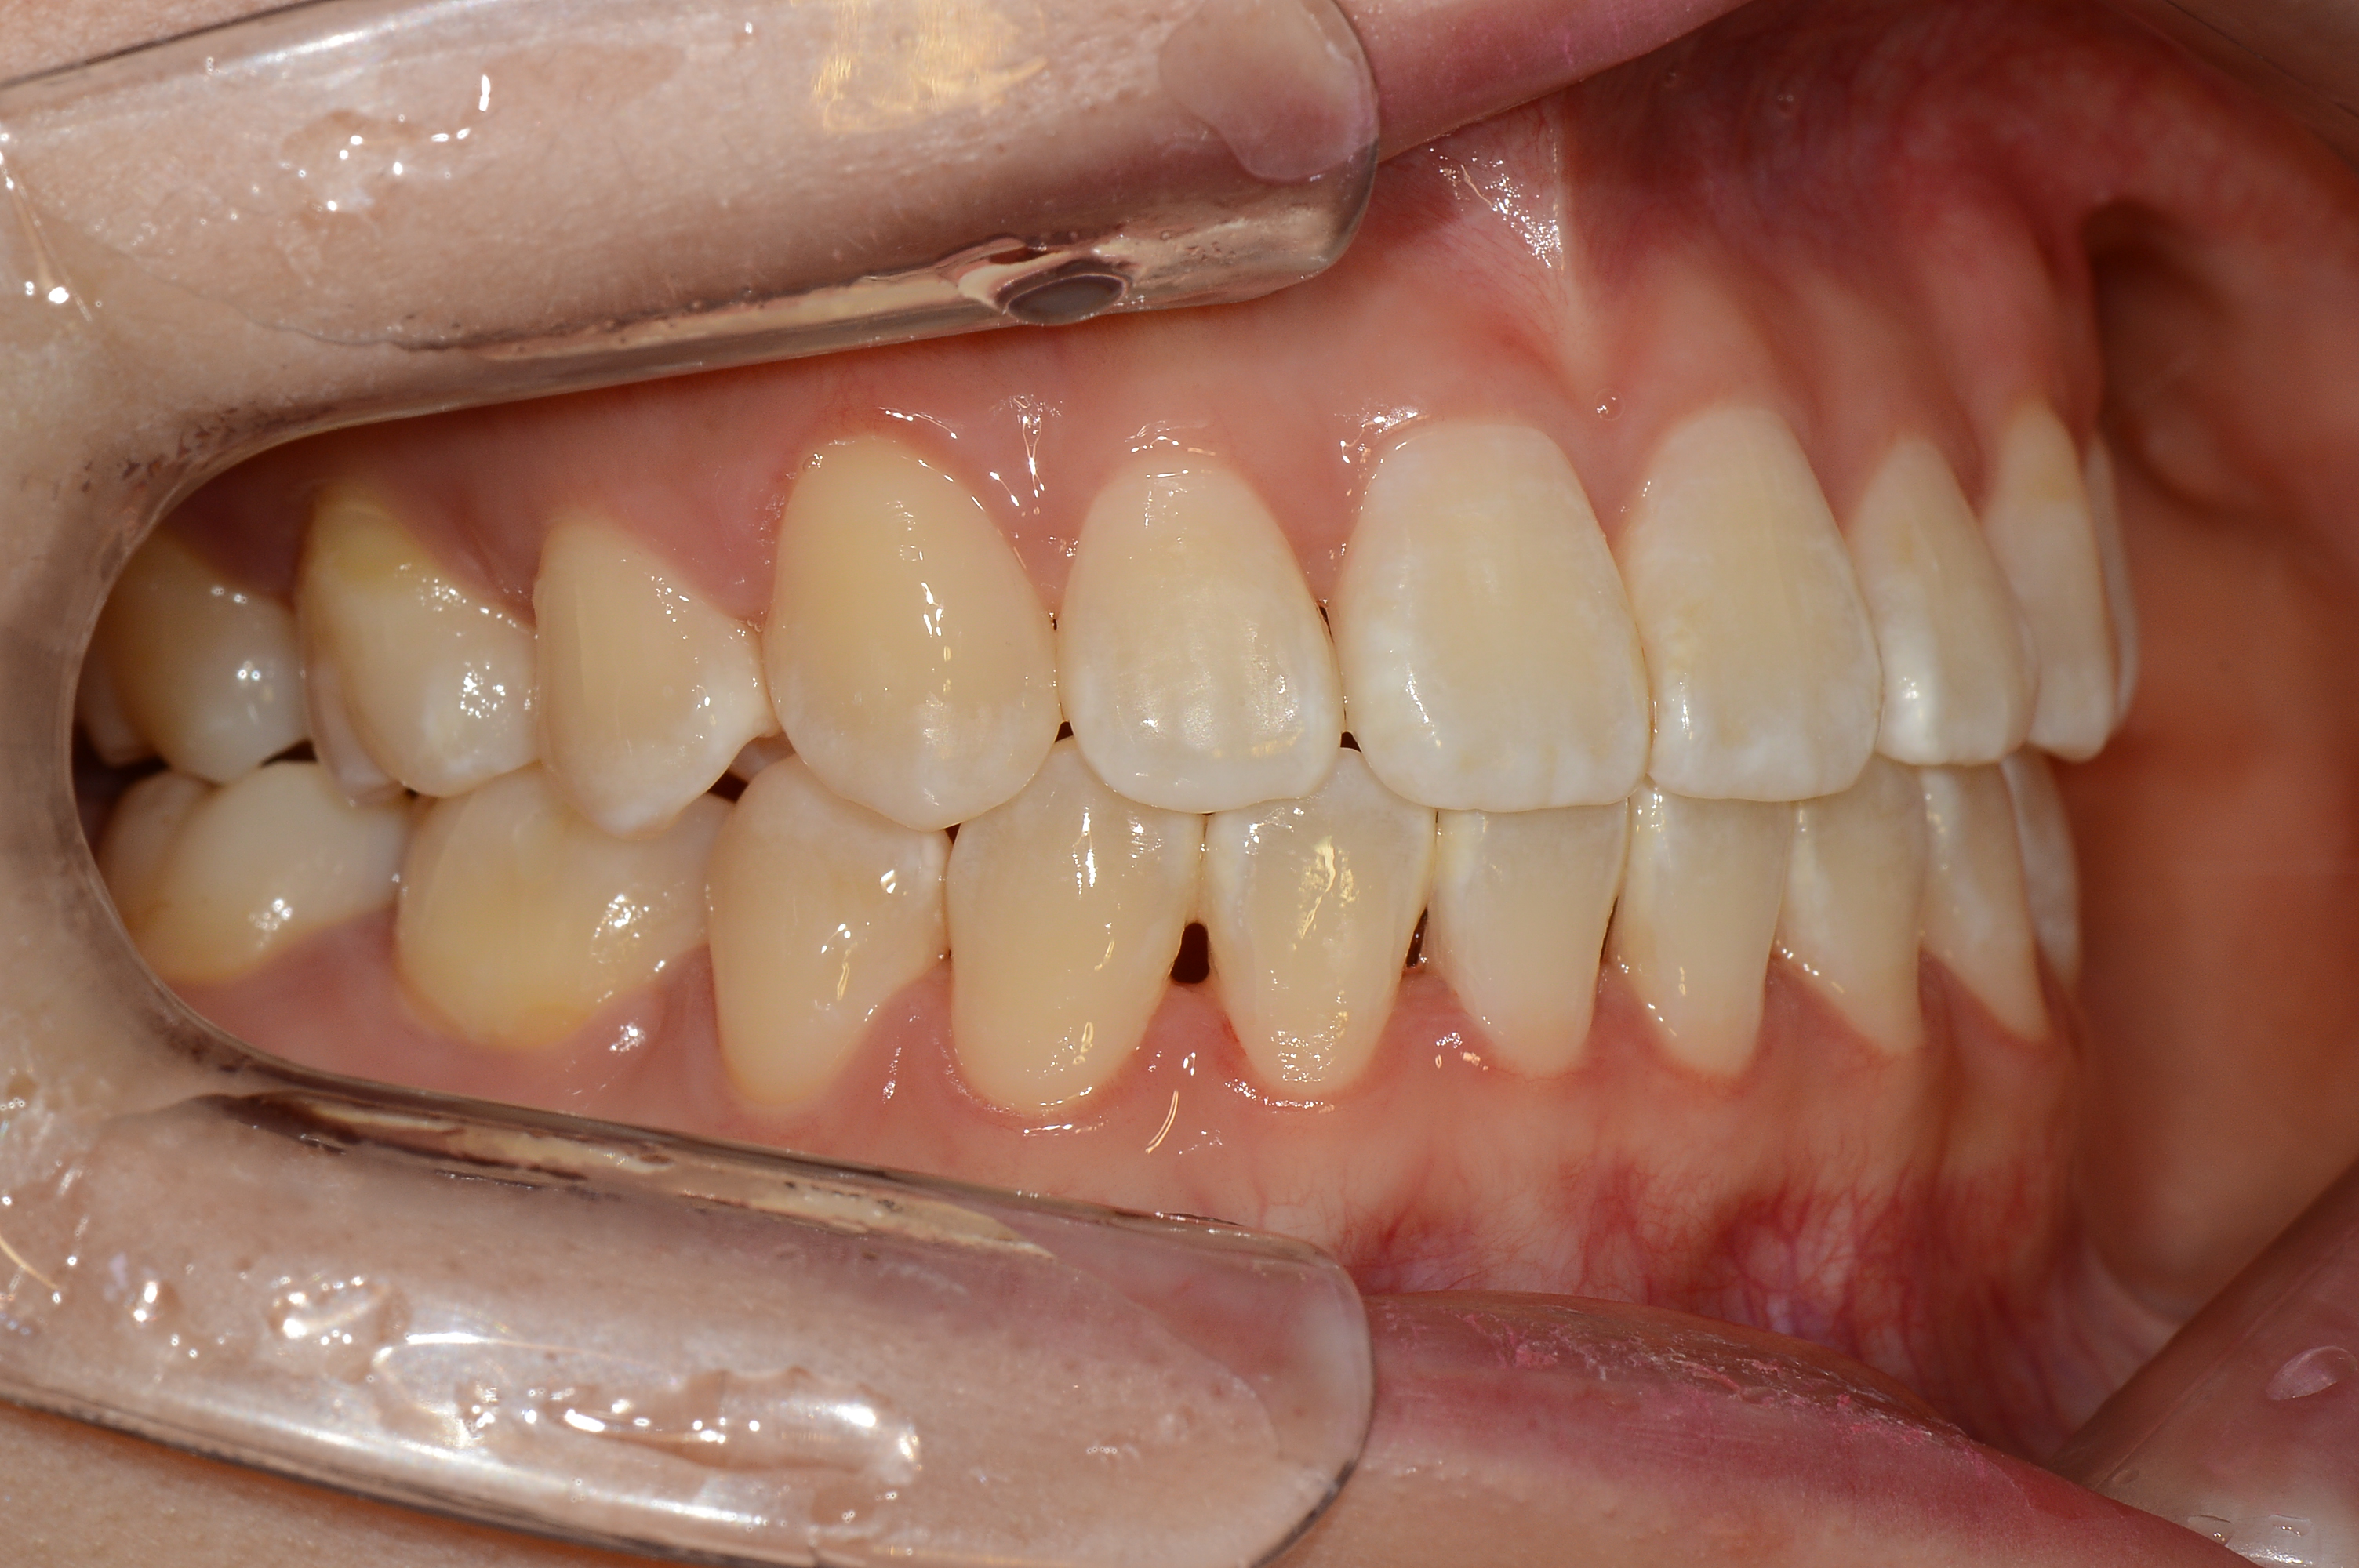

치료 전 사진입니다.